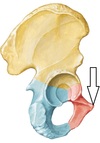

Iliofemural ligament